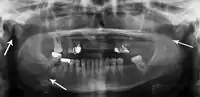

Panoramic radiography

Panoramic radiographs are tomograms where the mandible is in the focal trough and show a flat image of the mandible. Because the curve of the mandible appears in a 2-dimensional image, fractures are easier to spot leading to an accuracy similar to CT except in the condyle region. In addition, broken, missing or malaligned teeth can often be appreciated on a panoramic image which is frequently lost in plain films. Medial/lateral displacement of the fracture segments and especially the condyle are difficult to gauge so the view is sometimes augmented with plain film radiography or computed tomography for more complex mandible fractures.

Panoramic radiograph of a simple mandible fracture of the right mandibular body, minimally displaced. Note that the teeth to the left of the fracture do not touch